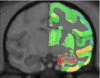

We present unbiased standard macaque monkey magnetic resonance imaging template brain volumes that offers a common stereotaxic reference frame to localize anatomical and functional information in an organized and reliable way for comparison across individual nonhuman primates and studies.